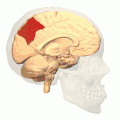

Medial surface of left cerebral hemisphere. (Precuneus visible at top left.) (Anterior to the right.)